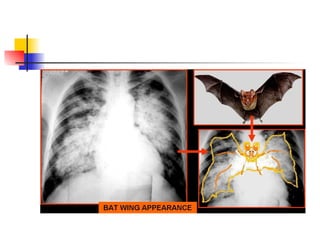

Alveolar consolidation of the

“bats –wing pattern”

 a) acute:

 - Pulmonary oedema

 b) chronic:

 - Lymphoma/leukaemia

 - Sarcoidosis but the interstitial form

is much commoner

 - Pulmonary alveolar proteinosis

 - Alveolar cell carcinoma but the

localised form is much commoner

Alveolar consolidation: bats

wing